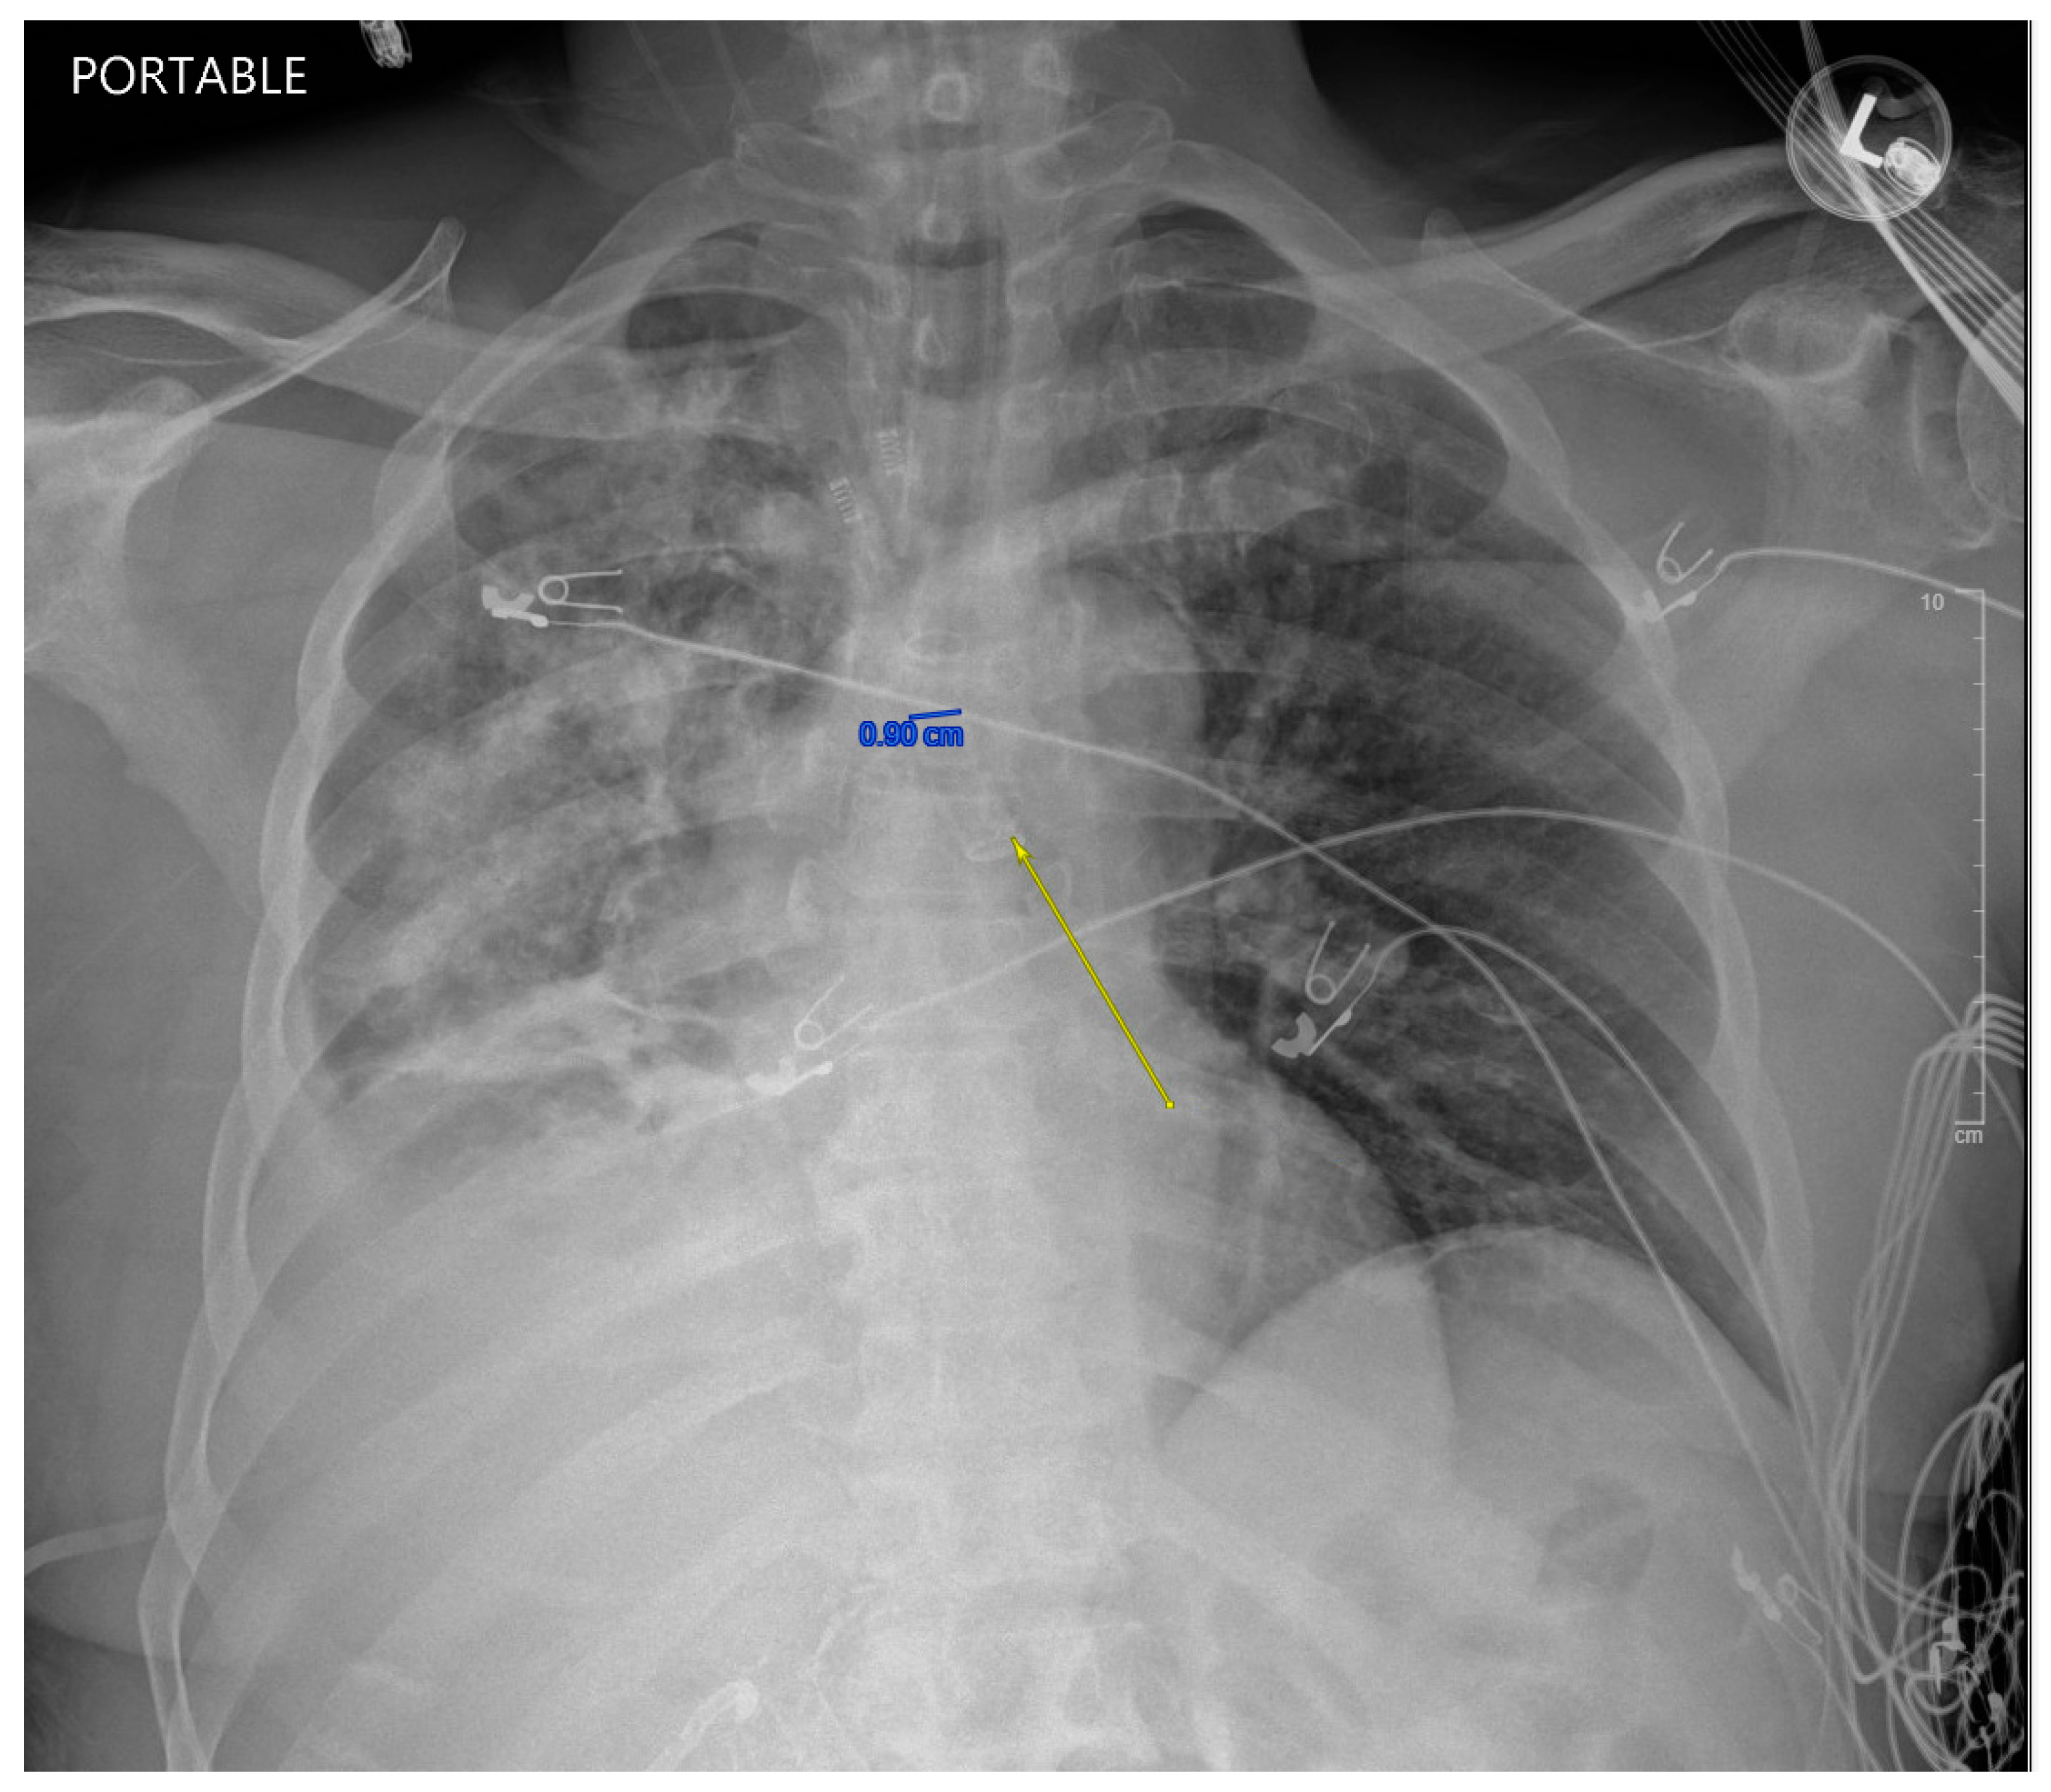

Figure 2. AP chest X-ray demonstrating DLT and infiltrated right lung with preservation of the left lung on admission to MICU. The yellow arrow demonstrates left bronchus intubation and a protected left lung compared to a patchy and opaque right lung from bilious contents entering the right airway.

While in the MICU, the patient was weaned off pressors, and IP conducted another bronchoscopy, which showed thick, bloody secretions in the right lower lobe airway. There were no obvious secretions in the left airway. Therapeutic suctioning was performed. The patient remained intubated during post-operative day one and was started on a five-day course of Zosyn given the acute infiltrations seen on chest X-ray in the right lung (see Figure 2). Bile cultures were negative. The patient was extubated on post-operative day two with the difficult airway team present. The patient was alert and oriented to person, place, and time with appropriate biliary drain function (200 cc/day) and ambulating with assistance (ICU mobility level 8). In April 2024, the patient underwent a staging cholangiogram with internalization of the biliary drain (see Figure 3). Finally, the patient underwent a successful embolization of the biliary-pleural fistula in March 2024.